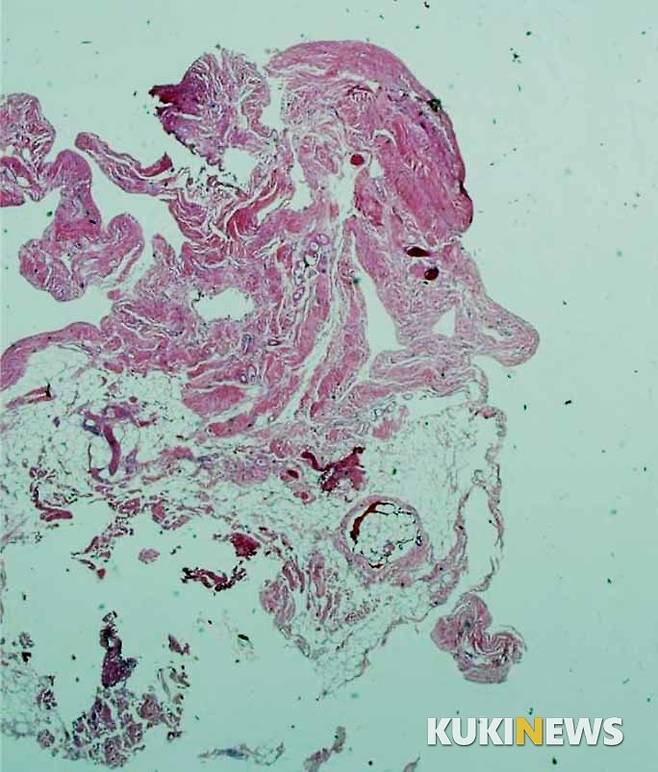

늘 사진에 관심이 많던 그에게 1993년 어느 날, 재미교포 병리과 교수의 피부암 특강이 끝날 무렵 마지막 슬라이드 사진 속 암세포가 환하게 웃는 모습을 보고 김 교수는 전율을 느꼈다. “아∼ 세포가 웃고 있네! 나도 저런 사진 한번 찍어봐야겠다”고 결심이 선 김 교수는 영국에 연수를 다녀온 직후인 1995년 당시 거금 이천만원을 주고 현미경을 구입했다. 김 교수는 환자의 세포를 꼼꼼하고 정확하게 살피며 병의 유무, 병명, 원인균 등을 찾아내는 일이 우선이지만 틈틈이 조직 속에서 특이한 형태의 사진 형상이 나타나면 하나 둘씩 저장해 나갔다.

출근해서 현미경 속을 들여다보는 일이 행복하다는 그는 “젊어서는 단지 자신의 업무에 충실하느라 이른 아침부터 늦은 밤까지 현미경을 들여다보고 살았지만 현미경 속에서 또 다른 세상을 발견한 후로는 일상이 너무 즐겁고 감사하다”고 말한다. 현미경에 눈을 대고 작은 유리판 위에 붙어있는 조직이나 점액질 검사를 하다보면 어느 날은 ‘노래 부르는 사람의 얼굴’과 길쭉한 모양이 된 석면에서 ‘무사의 검’이 나타나고 어떤 날은 ‘불 속으로 뛰어드는 불나방’이, 또 어느 날은 ‘여인의 우아한 춤사위’가 그의 눈에 들어왔다. 그는 20여 년간 미세한 조직과 세포 속에서 구상과 비구상의 무수한 작품들을 찾아냈다.

김 교수의 작품이 알려지기 시작한 것은 2013년 충청북도가 주관한 바이오사진전에서 교육과학기술부장관상을 받으면서부터다. 무릎관절 연부조직 중 일부를 100배 확대해 얻은 ‘흰 수염 할아버지’라는 작품이다. 2016년에는 그간의 세포 탐미와 기록이 담긴 개인전 ‘Nomad in a small world展’을 열었다. 그동안 일반 사진전에서는 볼 수 없었던 특이한 김 교수의 사진전은 관람객의 호기심과 감탄을 자아내기에 충분했다. 전시회 수익금은 전액 호스피스재단에 기부했다.